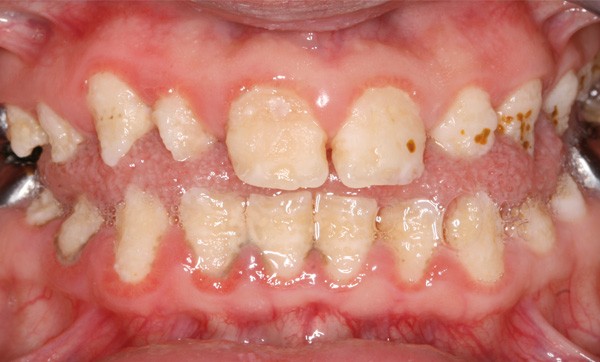

Sur le plan phénotypique, il existe 4 formes reconnues d’amélogenèse imparfaite : hypoplasique, hypomature, hypominéralisée et mixte [6]. La forme hypoplasique est caractérisée par un émail d’épaisseur réduite, dont la surface peut présenter des puits ou des fissures. Dans la forme hypominéralisée, l’émail est friable, décoloré et s’élimine rapidement. Dans le type hypomature, l’émail a un aspect opaque et crayeux. Ces défauts amélaires peuvent être associés à des problèmes éruptifs, une attrition sévère, une perte de dimension verticale d’occlusion (DVO) et des problèmes de béance [7]. Si les complications les plus sévères se rencontrent dans la forme hypominéralisée, les doléances esthétiques sont toujours exprimées par les patients, quelle que soit la forme d’amélogenèse imparfaite [8]. Radiologiquement cette affection se manifeste par des couronnes de morphologie altérée, parfois une disparition de la couche d’émail ou un émail de densité similaire à celle de la dentine.

Reposant sur l’examen clinique et radiographique, le diagnostic est parfois difficile du fait de la variabilité des caractères phénotypiques [9]. Il doit pourtant être réalisé précocement, afin de débuter idéalement le traitement en denture lactéale [10]. Le traitement esthétique et fonctionnel varie en fonction de la sévérité de l’atteinte : reconstitutions coronaires partielles (composites, inlays, facettes)…